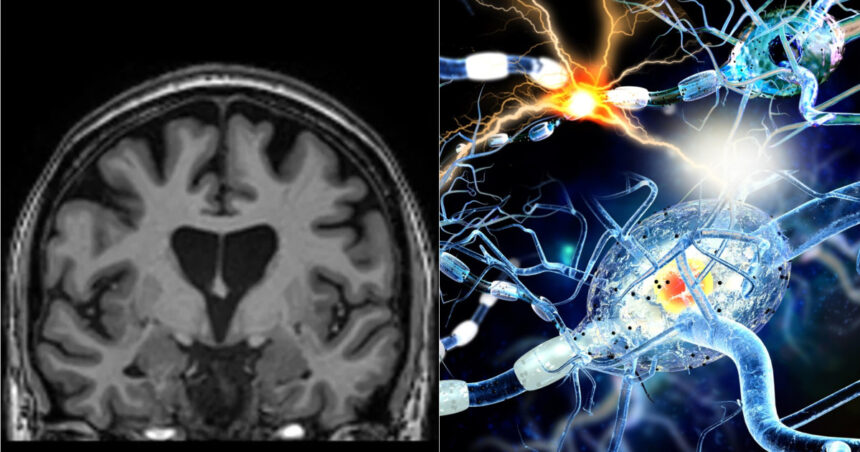

COVID-19 este cunoscută în principal ca o boală respiratorie, însă tot mai multe date științifice arată că efectele sale pot depăși plămânii. Un nou studiu sugerează că infecția cu SARS-CoV-2 poate produce modificări măsurabile la nivelul creierului, chiar și la persoanele care se consideră complet vindecate și nu mai prezintă simptome.

Cercetarea a fost realizată de o echipă de la Universitatea Griffith, în cadrul Centrului Național pentru Neuroimunologie și Boli Emergente (NCNED), și a folosit tehnici avansate de rezonanță magnetică (RMN) pentru a evalua sănătatea creierului la persoanele care avuseseră COVID-19. Rezultatele au fost comparate cu cele ale unor participanți care nu au fost infectați cu virusul.

Analiza imaginilor RMN a arătat semne clare că o infecție anterioară cu SARS-CoV-2 poate lăsa urme detectabile în creier, inclusiv atunci când participanții nu raportau simptome persistente. Potrivit cercetătorilor, acest lucru sugerează că efectele virusului pot continua dincolo de faza acută a bolii, fără a fi neapărat evidente clinic.

Echipa a utilizat imagistică multimodală pentru a examina atât substanța cenușie, cât și substanța albă, regiuni esențiale pentru memorie, funcții cognitive și sănătatea generală a creierului. Diferențe clare au fost identificate între grupurile de participanți, inclusiv între cei considerați complet recuperați și persoanele care nu au avut COVID-19.

Investigațiile RMN au evidențiat modificări importante ale substanțelor chimice din creier, ale intensității semnalului și ale structurii țesutului cerebral. Aceste schimbări au fost observate nu doar la persoanele cu sindrom post-COVID (COVID de lungă durată), ci și la cele care se considerau vindecate complet. În plus, cercetarea a arătat că gradul de modificare a țesutului cerebral a fost asociat cu severitatea simptomelor la persoanele cu sindrom post-COVID, susținând ipoteza unor efecte persistente asupra sănătății creierului.

Rezultatele se adaugă unor cercetări anterioare care sugerează că virusul SARS-CoV-2 poate persista în creier și poate deregla activitatea neuronilor. Alte studii au indicat că infecția ar putea genera modificări similare celor observate în boala Alzheimer, inclusiv la nivelul creierului și al retinei.

Noile date oferă indicii importante despre modul în care SARS-CoV-2 afectează sistemul nervos central și pot contribui la înțelegerea problemelor cognitive raportate de pacienți, precum dificultăți de memorie și concentrare, atât la scurt timp după infecție, cât și la luni sau chiar ani distanță.